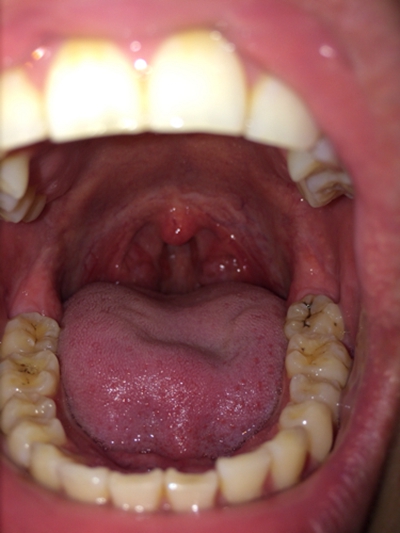

口腔念珠菌感染 (47)